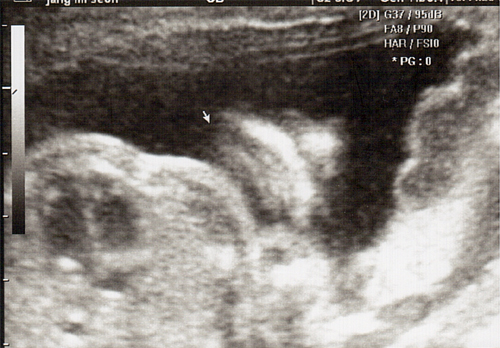

강아 ^^ 21주 강이의 정밀 초음파를 봤어 일반 초음파 보다는 더 정밀하게 나오더라구 엄청 커버린 강이가 한눈에 보이지 않을정도로 이제는 초음파 기계가 작아 보이더라..

강이 얼굴을 딱~ 보는순간.. 심장이 멈추고 코를 보는순가 다시 심장이 뛰기 시작했어 딱.. 아빠 코를 닮았더라 ^^:.. 이쁜자식...